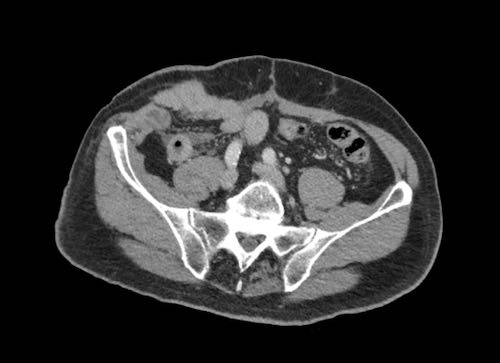

Cuộn xem ảnh CT

Ca lâm sàng 1

Cuộn qua các lát cắt.

Bạn có thể phát hiện tất cả các tổn thương cấy ghép phúc mạc không?

Bệnh nhân này đã được phẫu thuật và toàn bộ phúc mạc được ghi nhận phủ kín bởi các tổn thương u dạng kê.